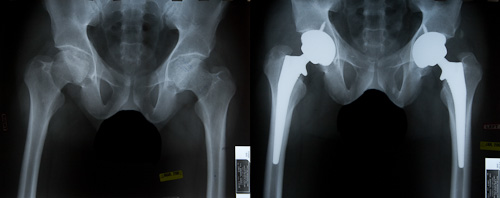

Primary total hip replacement is performed to treat chronic hip pain and limited mobility. It replaces the damaged joint with a durable artificial implant, helping patients regain natural movement and long-lasting relief.